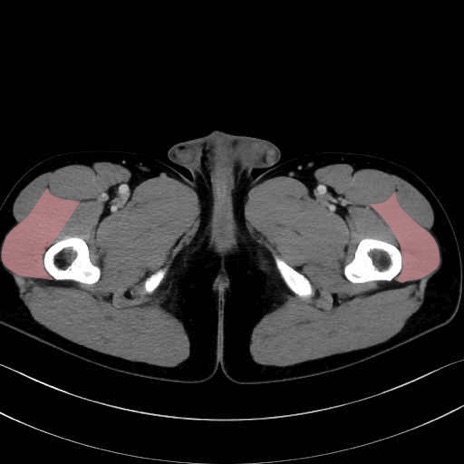

外側広筋(vastus lateralis) のCT画像の解剖

外側広筋 (Vastus lateralis)